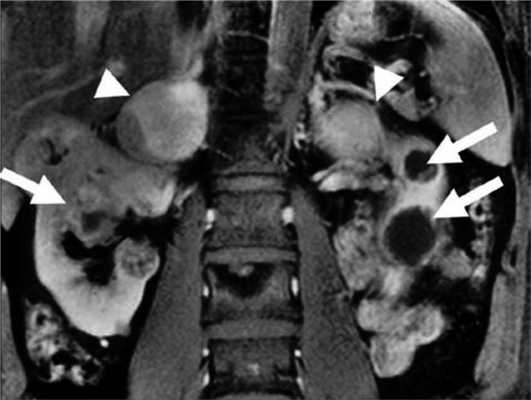

У пациентов с синдромом VHL могут встречаться как кисты, так и рак почек [57—62]. Средний возраст манифестации — 37 лет. Для диагностики используют КТ и УЗИ [36, 63, 64]. Поскольку со`лидные раки могут содержать кистозные части (что затрудняет дифференцирование доброкачественных и злокачественных процессов с помощью визуализирующих методик), при отсутствии данных о метастазах лечение должно быть направлено на удаление этих образований по возможности с соблюдением принципа органосохраняющей операции. Это позволяет поддерживать почечную функцию максимально долго и избежать диализа [58, 65]. Опухоли почек отличаются медленным ростом (3 см (по стандартам США) или 5 см (по стандартам Европы) [58, 60, 67, 68]. Некоторые авторы [69] сообщают о высоком риске местного рецидива (приблизительно 50%) в среднем в течение 53 мес (диапазон 10—115 мес) и росте опухоли со скоростью 34 мм/год (диапазон 1—10,8 мм). «Золотым» стандартом лечения небольших опухолей является открытая и лапароскопическая частичная нефрэктомия. В настоящее время используются также альтернативные методы — криотерапия и радиочастотная аблация [70]. Последние методы могут повлиять на результат патоморфологического диагноза, хотя, по некоторым данным, патоморфологический диагноз после первого цикла криотерапии приблизительно в 91% случаев подтверждает результаты предварительной биопсии [71].

Феохромоцитома выявляется примерно у 26% пациентов с синдромом VHL [37]. У пациентов с очевидно спорадической феохромоцитомой в 3—11% случаев впоследствии выявляют мутацию VHL [10, 12, 13]. Феохромоцитома может быть первым проявлением синдрома [30, 72]. В большинстве случаев надпочечниковые феохромоцитомы при VHL-синдроме двусторонние (синхронные или метахронные) [37, 73]. Вненадпочечниковые феохромоцитомы встречаются примерно в 30% случаев [37, 74—76]. Феохромоцитомы как часть синдрома VHL имеют исключительно норадреналиновый фенотип. Биохимические маркеры опухоли могут помочь отличить VHL-ассоциированные феохромоцитомы от феохромоцитом при синдроме МЭН 2-го типа [75]. Различия в биохимическом фенотипе при VHL-синдроме и МЭН 2-го типа связаны с различной экспрессией тирозингидроксилазы (TH) — лимитирующего фермента синтеза катехоламинов, и фенилэтаноламин-N-метилтрансферазы (PNMT). У пациентов с синдромом VHL отмечена низкая экспрессия PNMT, преобразующей норадреналин в адреналин. Различия биохимического фенотипа также связаны с различиями хранения, транспорта и секреции катехоламинов [77]. МЭН 2-ассоциированные феохромоцитомы содержат более высокие концентрации катехоламинов из-за более выраженной экспрессии TH. VHL-ассоциированные феохромоцитомы, секретируют катехоламины непрерывно, тогда как при синдроме МЭН 2 отмечен эпизодический характер секреции. Это определяет и различия клинических проявлений двух синдромов. Например, пациенты с МЭН 2 чаще жалуются на кризовые подъемы АД [78]. Помимо генетических различий [26], регистрируется разная экспрессия эритропоэтина и его рецептора [79]. Кроме того, около 80% феохромоцитом бессимптомны и выявляются случайно при визуализирующих исследованиях. Низкая чувствительность некоторых радионуклидных методов визуализации может объясняться относительной нехваткой гранул хранения или уменьшенной экспрессией мембранного норадреналина или везикулярных моноаминных транспортеров [80]. Поэтому сцинтиграфия с 123 I-MIBG (метайодбензилгуанидином) часто не обнаруживает VHL-связанные надпочечниковые феохромоцитомы [81, 82]. ПЭТ с 6-18F-фтордопамином более чувствительный метод [36, 83]. Злокачественные феохромоцитомы с метастазами в легких, печени, костях, лимфоузлах редко встречаются при синдроме VHL [37, 74, 84—87]. Метастазы выявляются менее чем в 7% случаев [37]. К сожалению, в настоящее время нет четких признаков, позволяющих надежно отличить доброкачественную от злокачественной феохромоцитомы, хотя уже известно, что герминальная мутация гена SDHB, является в этом отношении точным маркером [86—88]. Выявление феохромоцитомы у пациентов с синдромом VHL особенно важно, учитывая высокую вероятность хирургических вмешательств по поводу других опухолей (гемангиобластом ЦНС и др.). Невыявленная феохромоцитома при других вмешательствах может привести к опасным для жизни гипертоническим кризам. Более 70% феохромоцитом у детей являются VHL-ассоциированными. Каждому пациенту с VHL-синдромом и подтвержденной феохромоцитомой до оперативного лечения необходимо проводить ПЭТ с 6-18F-фтордопамином или сцинтиграфию с 123 I-MIBG для выявления вненадпочечниковой феохромоцитомы или метастазов [89]. Лечение феохромоцитомы оперативное. В то же время 6-месячная терапия ингибиторами тирозинкиназы приводит к уменьшению опухоли на 21% и сокращению уровня норметанефринов и хромогранина А в плазме [90] (рис. 4). Рисунок 4. Двусторонняя феохромоцитома и поликистоз почек.